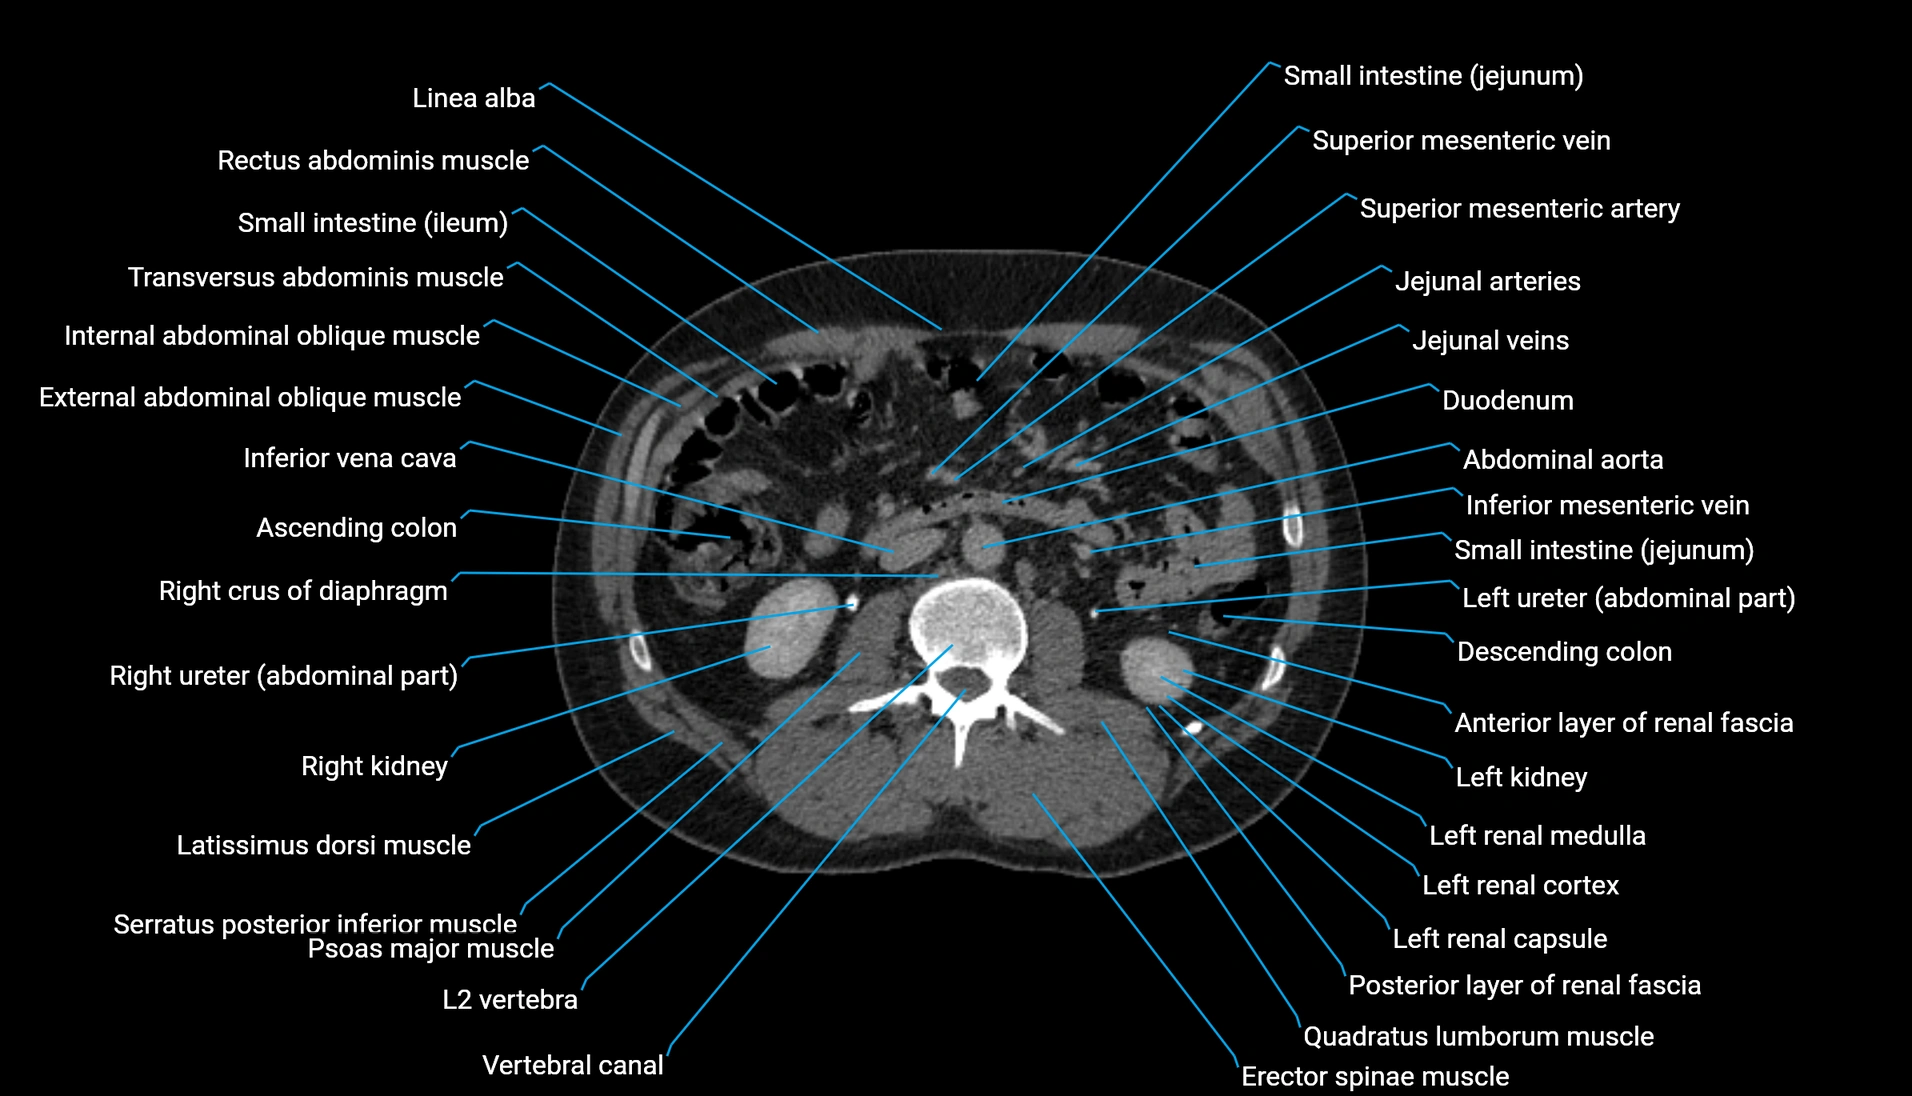

CT Appearance

Non-contrast CT:

-

Demonstrates cortical bone of acetabular rim in excellent detail

Detects fractures, dysplasia, retroversion, or bony overcoverage (pincer impingement)

3D reconstructions used in preoperative hip surgery planning

CT image